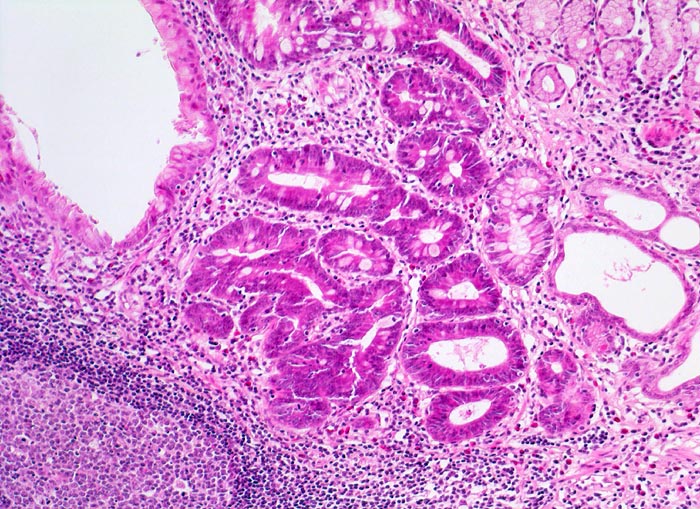

PathoPic – image database / PathoPic ID 5115 - Chronische Helicobactergastritis: intestinale Metaplasie

Chronische Helicobactergastritis: intestinale Metaplasie

Magenantrumschleimhaut mit dichtem Entzündungsinfiltrat mit Lymphfollikelbildung in der Lamina propria. Das Epithel eines Teils der Drüsen weist deutlich dichteres Zytoplasma mit Einschluss einzelner Becherzellen auf entsprechend einer intestinalen Metaplasie. Einzelne dilatierte Drüsen (= Magendrüsenkörperzysten).

Lymphfollikel sind typisch für die Typ B Gastritis. Die intestinale Metaplasie hingegen ist unspezifisch. Sie kann auch nach Abheilung von Ulzera und Erosionen oder bei einer Autoimmungastritis auftreten. Eine Unterscheidung von kompletter und inkompletter Metaplasie ist nur mittels Spezialfärbungen eindeutig möglich und wird wegen fehlender klinischer Relevanz nicht vorgenommen.

Magendrüsenkörperzysten können dem Endoskopiker als kleine Polypen erscheinen